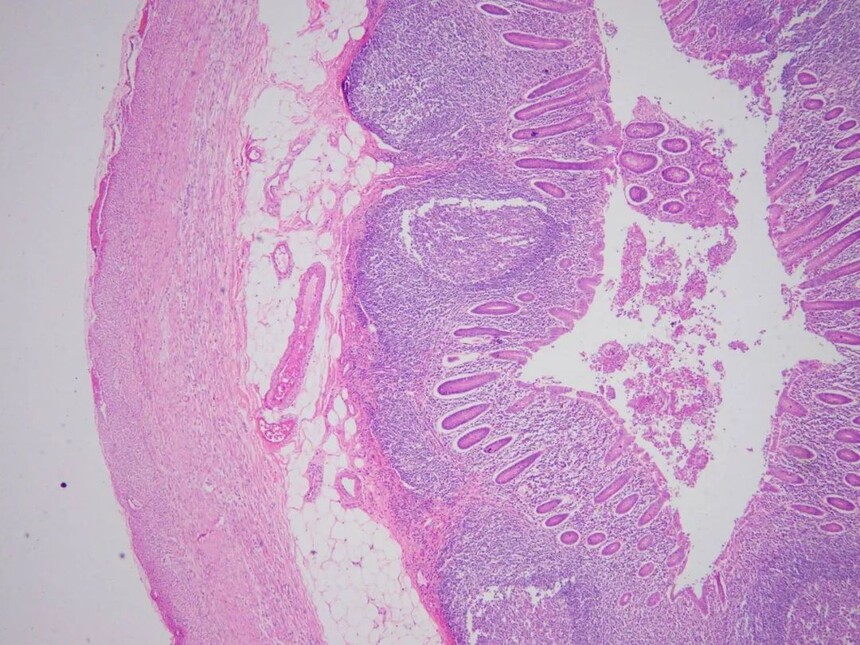

6、急性蜂窝织性阑尾炎

阑尾横断面组织切片局部放大,可见黏膜层、粘膜下层、肌层及将膜层内。血管充血水肿,阑尾壁全层有大量中性粒细胞弥漫性浸润。部分区域黏膜上皮细胞坏死脱落。